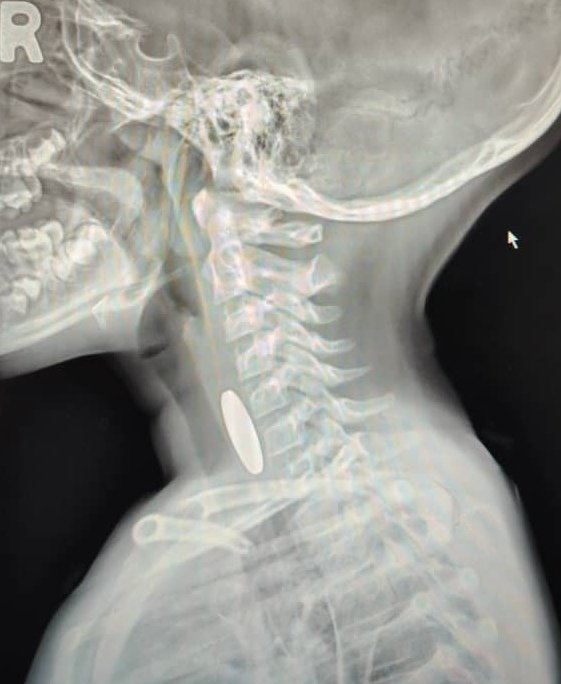

他说,X光扫描后显示,小孩的食道里卡着一枚如钱币的东西。然而,经过检查和手术后,他惊讶地发现该异物竟然是一枚游戏机的硬币。

莫哈末沙依夫指出,因为小孩误吞钱币很常见,所以当下他就以为该小孩误吞了钱币,没想到居然是一枚游戏机的硬币,幸好最后成功取出。